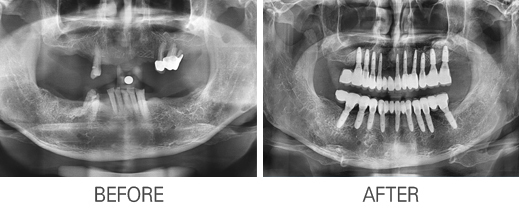

Ä«Å×°í¸®

: Àüü ÀÓÇöõÆ®

Á¦¸ñ